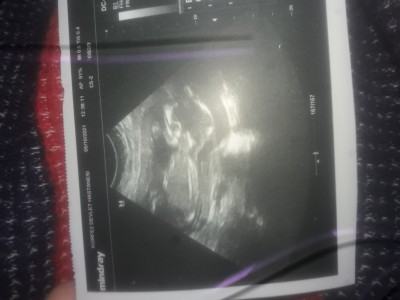

Cinsiyet tahmimi

Sizce nedir

Erkek sanki çok anlamam ama

Kız geçti içimden

Hadi bend3 erkek dyim :D

Kız diyorum bende:) belli olunca haber edersiniz sağlıklı olsun en başta♥️

bence kiz .